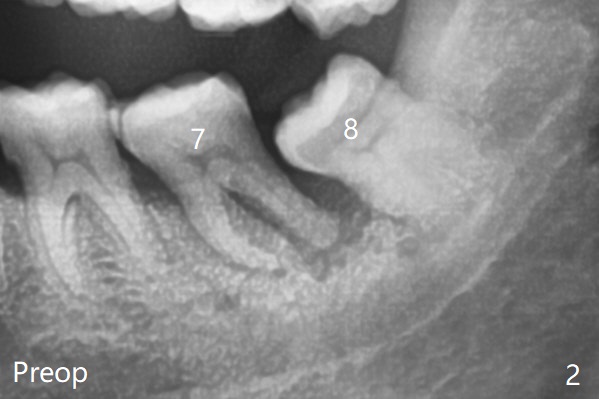

因此8拔出后,牙槽窝塞入胶原塞(图五:C),将粘性骨粉放置7近中,远中(图五:白*)以及颊侧(黑*),